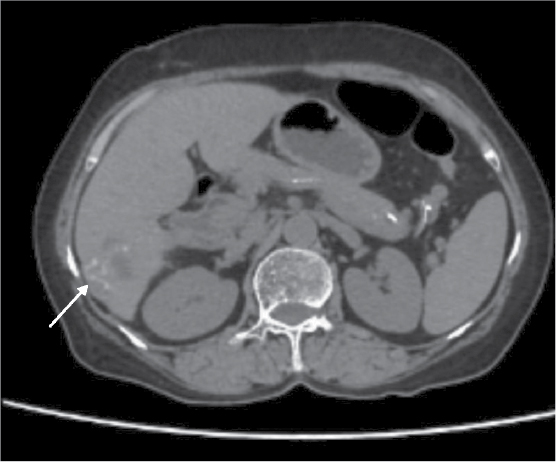

A differential diagnosis of resolving liver abscess or pancreatic pathology was considered. Further evaluation with 640-slice computed tomography (CT) abdomen showed multiple peripherally enhancing lobulated lesions with internal calcifications involving segments 6, 7 and 8 of right hepatic lobe (Fig. 1 a-f). Few lesions appeared tubular/serpiginous and were located in the subcapsular region (Fig. 2). Imaging was in favor of liver trematodes as the cause of liver abscess. A liver biopsy was done and histopathology of the tissue showed necrotic liver parenchyma with degenerated parts of parasite, likely a trematode (Fig. 3 a and b). Gram stain, acid-fast stain, fungal stain, Xpert Mycobacterium tuberculosis and tissue culture and sensitivity of the sample were negative. Since liver function tests were normal, endoscopic retrograde cholangiopancreatography (ERCP) was deferred and a decision to start medical management was taken. Patient was started on oral nitazoxanide 500 mg 3 times a day for 3 weeks. During follow-up, the patient was found to have no further fever spikes and her right upper quadrant pain had significantly reduced.

Figure 2. Serpiginous lesion in the subcapsular region.